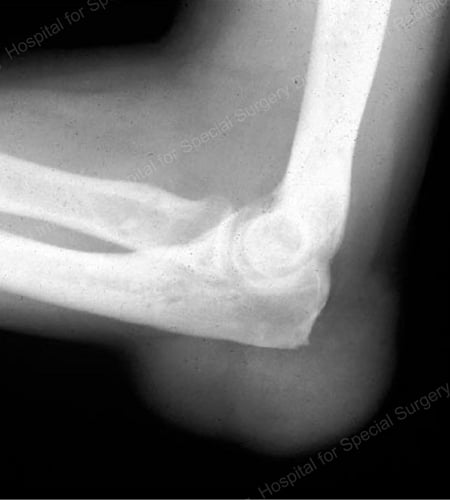

X-rays are the standard imaging technique for gout (See Figures 12-17: Figure 12: Gout of the Base of the 1st Toe; Figure 13: Gout of the Distal Finger Joints; Figure 14: Gouty Change and Soft Tissue Calcification About the Base of the 1st Toe; Figure 15: Gouty Destruction at Multiple Finger Joints; Figure 16: Gouty Erosion at the Proximal Ulna at the Elbow; Figure 17: Large Tophus Seen as Soft Tissue Mass at the Elbow) but in special cases, such as when gout needs to be separated from infection or tumor, magnetic resonance imaging (MRI) (Figure 18: MRI of the Knee Showing Gouty Soft Tissue Mass and Erosion of the Kneecap) or ultrasound (Figure 19: Power Doppler Study Showing Gouty Inflammation at the Base of the 1st Toe) will be helpful. A newer technique called a dual-energy CT scan (DECT) can show urate crystals in green color.

X-ray of gouty erosion at the proximal ulna at the elbow

Figure 16: Gouty Erosion at the Proximal Ulna at the Elbow

X-ray of a large tophus seen as soft tissue mass at the elbow

Figure 17: Large Tophus Seen as Soft Tissue Mass at the Elbow